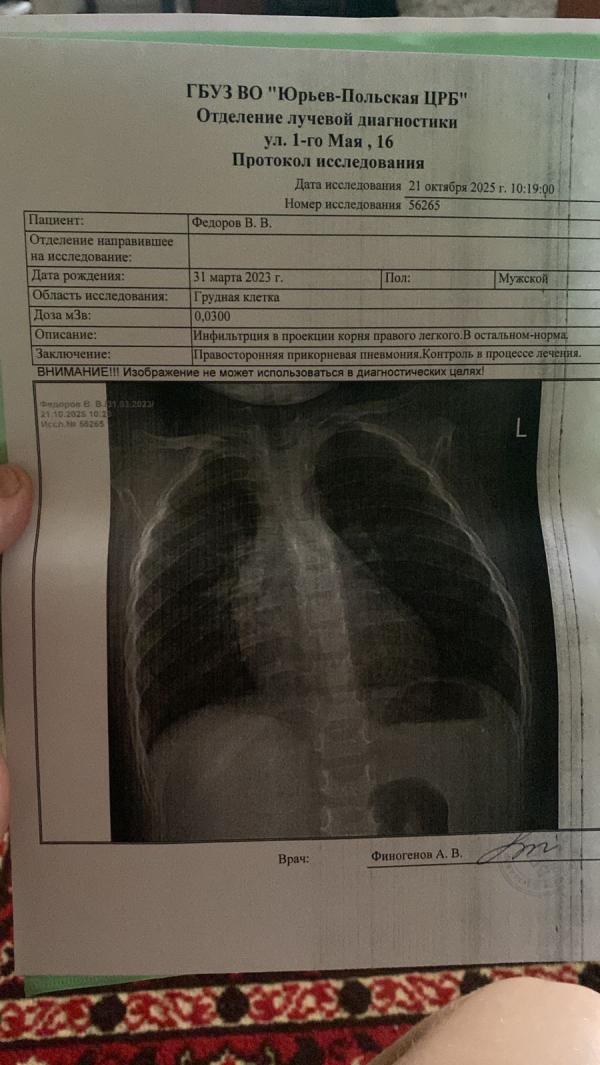

Прикорневая - не такая большая пневмония, но как она себя дальше поведёт - никто не знает. В инфекции - в каждой палате своя нозология.